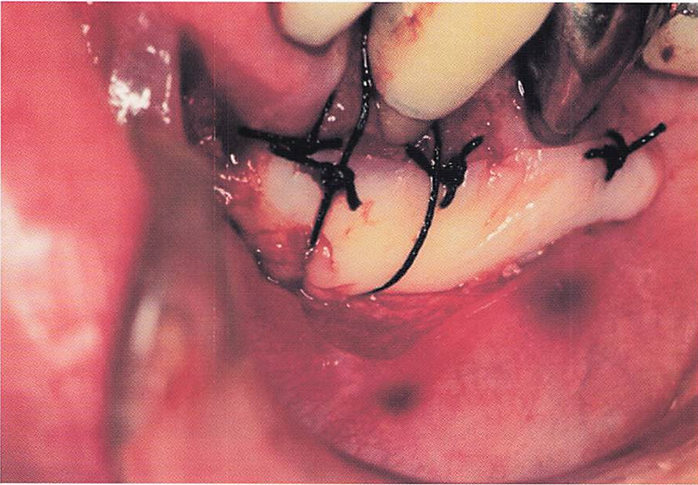

午後-44

45歳の女性。下顎左側小臼歯部の歯が伸びて見えることを主訴として来院した。歯周基本治療後に、下顎左側第一小臼歯の歯根露出に対して根面被覆を目的に歯周形成術を行うことになった。手術中の口腔内写真を別に示す。

行った手術はどれか。1つ選べ。

a.歯肉剥離掻爬術

b.遊離歯肉移植術

c.歯肉弁側方移植術

d.歯肉弁歯冠側移動術

解答を見る

b